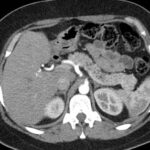

Paciente masculino de 35 años de edad, con antecedentes de tabaquismo, etilismo, consumo de sustancias psicoactivas. Ingresa al hospital de Sanatorio Franchin el 24 de mayo de 2024, donde se constata hipoglucemia severa con buena respuesta al glucosado hipertónico endovenoso. Al examen físico con la típica tríada de Whipple, dado por síntomas neuroglucopénicos de alteración del estado de conciencia, glucemia de 25 mg/dl y alivio sintomático después de la administración de glucosa. El paciente recupera el estado de conciencia y refiere dolor abdominal a nivel de epigastrio, por lo que se le realiza ecografía abdominal, donde se evidencia lesión nodular hipoecogénica en cuerpo del páncreas. Por esta razón se pasa al paciente a tomografía, donde se constata una formación nodular a nivel del cuerpo del páncreas, que presenta un ávido realce en fase arterial con homogeneización de la lesión en tiempo tardío.

Ahora bien, como se mencionaba al principio, el estudio ecográfico es de muy baja sensibilidad y se identifique o no la lesión por este estudio, nuestro siguiente paso en el algoritmo diagnóstico de esta lesión es la tomografía. Esta es la prueba no invasiva inicial, con una sensibilidad del 63% al 83%, y detecta del 70% al 80% de los tumores. Esta debe realizarse como un estudio trifásico: fase arterial temprana a los 30 segundos, fase venosa a los 70 segundos, fase tardía de 3 a 5 minutos. La característica de estos tumores por tomografía es que se presentan como una masa sólida que tiene un ávido realce en la fase arterial, cuyo realce se mantiene y se observa más tenue en la fase venosa y en los tiempos tardíos la lesión se homogeniza.

Para mi caso, y dando una visión general de los métodos de imagen no invasivos en esta revisión retrospectiva, solo a uno de los pacientes se le detectó la lesión por ecografía, donde se visualizó una lesión nodular hipoecogénica en el cuerpo del páncreas. A los demás pacientes se les detectó la lesión por tomografía en estudio trifásico, donde resaltan las características ya descritas por la literatura de lesiones hipervasculares con intenso realce en fase arterial, localizadas en diferentes partes del páncreas, como cabeza, cuerpo y cola.